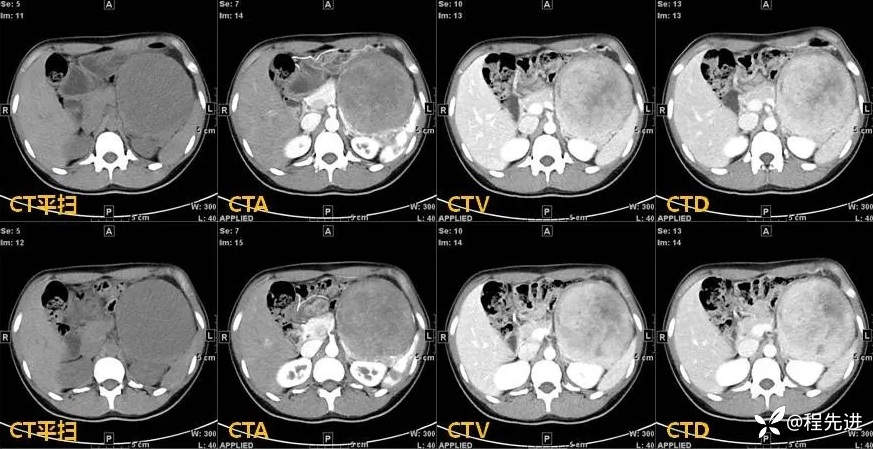

【现病史及既往史】:患者4天前于外院行CT检查发现胰腺肿物,胰胃间隙见一肿物,大小约108mmx103mmx122mm,考虑胰腺实性假乳头状瘤可能性大,无伴发热、畏寒,无恶心、反酸,无呕血、黑便。患者起病以来,一般情况可,无头晕、头痛,无心悸、气促,无腹泻、便秘,无排陶土样大便。精神可,胃纳、睡眠差,尿量如常,尿色淡黄,大便规律,体重未见明显改变。

影像检查: